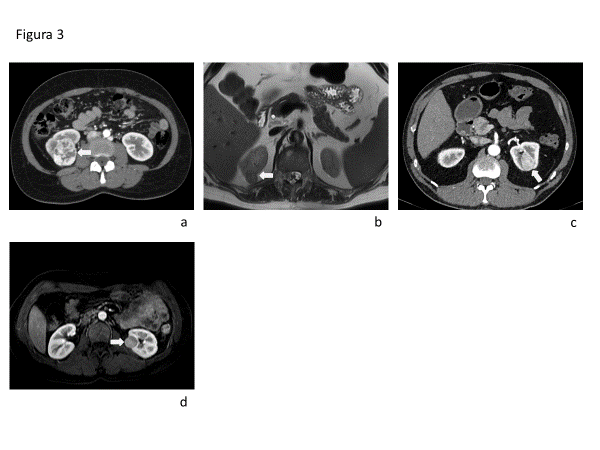

EL CCRcc presenta impregnación intensa con el contraste endovenoso tanto en TC como en RM en fase cortico medular, con lavado en fase nefrográfica en comparación con el parénquima renal. Los tumores de mayor tamaño son heterogéneos debido a la presencia de necrosis, hemorragia o elementos quísticos (Fig 3a). El CCRp es usualmente mas homogéneo e hipovascular. El patrón de realce dinámico permite diferenciar estas entidades con alta sensibilidad y especificidad(18).

En RM el CCRcc es de alta señal T2, mientras que el CCRp presenta hipointensidad de señal T2 (Fig. 3b). EL 60% de los CCRcc presentan grasa microscópica lo que se identifica por caída de señal en secuencia T1 gradiente en fase opuesta. Los CCRp por su parte pueden contener hemosiderina, lo que se manifiesta como caída de señal en T1 gradiente en fase.

La DECT permite la medición de concentración de yodo intratumoral, y se ha visto que permite distinguir entre CCRcc y CCRp. Usando como punto de corte 0,9mg/ml, se logra un área bajo la curva ROC de 0,92 (IC 95% 0,91-0,93), diferenciando CCRcc con mayor concentración, de CCRp con menor concentración respectivamente(17). Cuando los CCRchr no presentan una cicatriz central estrellada, ni áreas de patrón de realce invertido en secuencias dinámicas, son usualmente indistinguibles imagenológicamente de los CCRcc y de los oncocitomas (Fig. 3c y 3d).